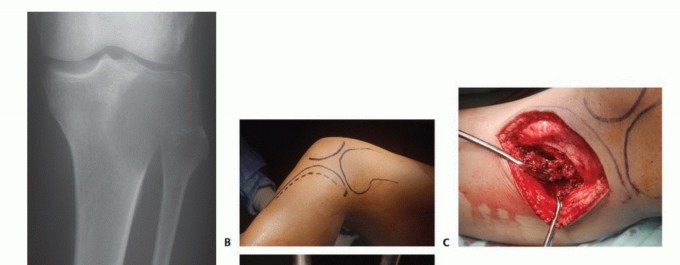

تُستخدم عادة لأورام العظام الحميدة، حيث يتم كشط الورم من داخل العظم، ثم يتم استخدام مواد مساعدة مثل الفينول أو النيتروجين السائل أو الكي الكهربائي لتدمير أي خلايا ورمية متبقية.

يُعد العلاج بالتبريد، خاصةً بتقنية الصب المباشر بالنيتروجين السائل، ثورة حقيقية في علاج أورام العظام، حيث يقدم بديلاً فعالاً وآمنًا للجراحات الكبرى، مع الحفاظ على الطرف المصاب ووظيفته. يعتمد هذا النهج على تدمير الخلايا السرطانية عن طريق تعريضها لدرجات حرارة منخفضة جدًا، مما يؤدي إلى تجميدها وموتها.

تقنية الصب المباشر بالنيتروجين السائل: تفاصيل الإجراء

تعتبر تقنية الصب المباشر بالنيتروجين السائل (Direct Pouring Liquid Nitrogen Technique) في العلاج بالتبريد لأورام العظام من التقنيات المتقدمة التي تتطلب دقة عالية وخبرة جراحية متخصصة. يفضل الأستاذ الدكتور محمد هطيف هذه التقنية نظرًا لفعاليتها في تحقيق تجميد عميق وشامل للورم، مع الحفاظ على الأنسجة السليمة المحيطة.

التحضير قبل الإجراء:

- التقييم الشامل: يقوم الدكتور هطيف بإجراء تقييم سريري دقيق، ومراجعة التاريخ المرضي للمريض، وإجراء الفحوصات التصويرية اللازمة (الأشعة السينية، الرنين المغناطيسي، الأشعة المقطعية، ومسح العظام) لتحديد حجم الورم وموقعه وعلاقته بالهياكل الحيوية المحيطة.

- الخزعة (Biopsy): في معظم الحالات، يتم أخذ خزعة من الورم لتأكيد التشخيص النسيجي وتحديد ما إذا كان حميدًا أو خبيثًا.